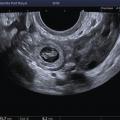

L’échographie, indispensable, doit examiner le pelvis mais aussi l’abdomen. Elle est donc réalisée par voie endovaginale, sus-pubienne et abdominale. On peut visualiser une masse latéro-utérine (fig. 1). Au sein de cet hématosalpinx, un sac gestationnel peut être visible, voire un embryon (fig. 2) ayant parfois une activité cardiaque positive. Le passage de la sonde à ce niveau est douloureux.

Souvent, le principal signe est indirect :

– vacuité utérine (fig. 3) et taux de hCG supérieur à 1 500 UI/L, fortement évocateurs. En cas de métrorragies, une lame d’hématométrie peut être visible en intra-utérin (« pseudo-sac gestationnel » : image hypo-échogène centrée dans la cavité, sans couronne trophoblastique) ;

Remerciements au Dr Gilles Grange, maternité Port-Royal, Paris pour les figures 1, 2 et 3.